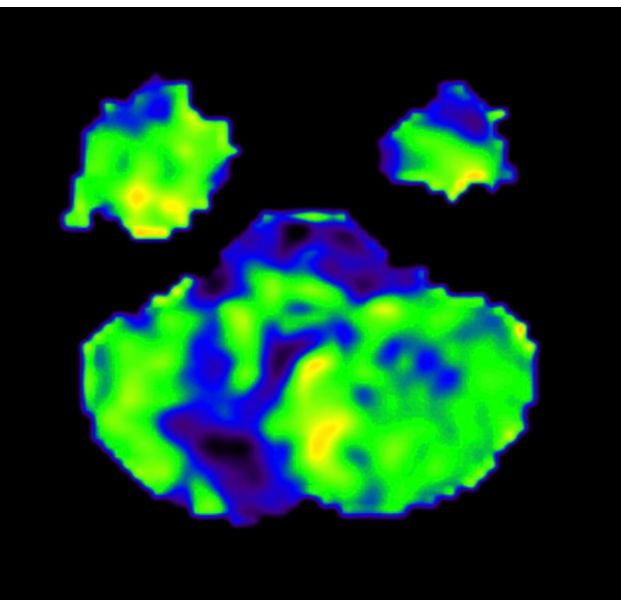

为寻求进一步治疗,家属慕名来到四川泰康医院神经外科苑玉清教授门诊。苑主任仔细分析病史及影像资料后,高度怀疑宁宁的“椎动脉闭塞”是导致症状的主因。入院后,医疗团队予以宁宁行头颅灌注磁共振检查发现有右侧小脑及脑干广泛血流灌注减少,随后安排完善DSA,最终确诊为“右侧椎动脉及右小脑下后动脉闭塞”。由于宁宁症状明显,保守治疗无效,手术成为最佳选择。

术后患者转入ICU监护,次日即转回普通病房。经过营养神经、改善循环等综合治疗,宁宁肢体麻木无力及吞咽呛咳症状明显改善,术后复查显示新建血管区域贴敷良好,无明显压迫性水肿及出血,脑血流得到有效改善。目前宁宁已康复出院。 主治医师孙医生讲,“术后恢复很好,比想象的快!” 。